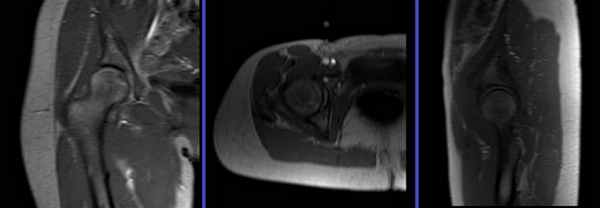

Положение для проведения исследования после внутрисуставного введения контраста

- Положение пациента лежа на спине головой по направлению к магниту (на спине головой вперед), предайте бедру небольшую внутреннюю ротацию;

- Расположите пациента над изогнутой катушкой и закрепите катушку над тазобедренным суставом (пораженной стороны);

- Надежно закрепите изогнутую катушку с помощью фиксаторов для предотвращения образования респираторных артефактов;

- Для дополнительного комфорта дайте пациенту подушку под голову (однако не подкладывайте валик под ноги);

- Центральный луч лазера фокусируется над тазобедренными суставами (на 4 дюйма ниже подвздошного гребня).